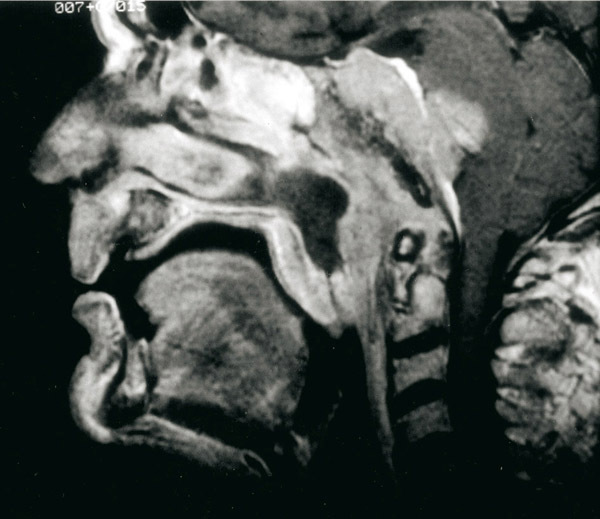

IRM incidence sagittale du nasopharynx. Carcinome indifférencié du nasopharynx étendu au sphénoïde et en intracrânien.